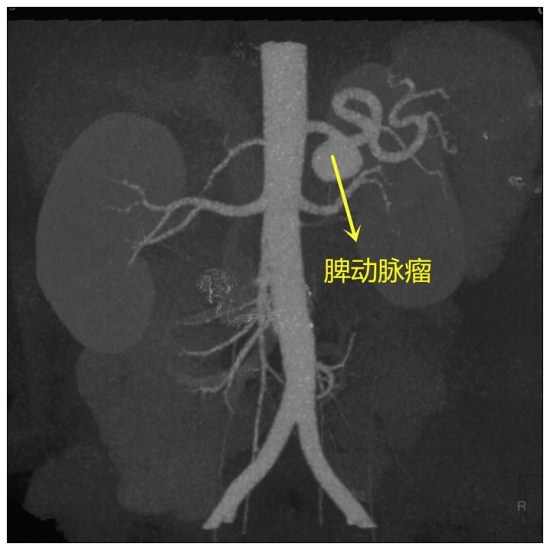

脾动脉瘤在内脏动脉瘤疾病中发病率最高,常在体检和破裂时发现,破裂后如不及时治疗,死亡率极高,是血管外科常见疾病之一。

近日,普外血管病区成功为一位脾动脉瘤患者施行了微创介入脾动脉瘤腔内隔绝术,创口仅腹股沟一处穿刺针眼,术后第二日即康复出院。取得完美的微创疗效,为更多的脾动脉瘤患者带来福音。